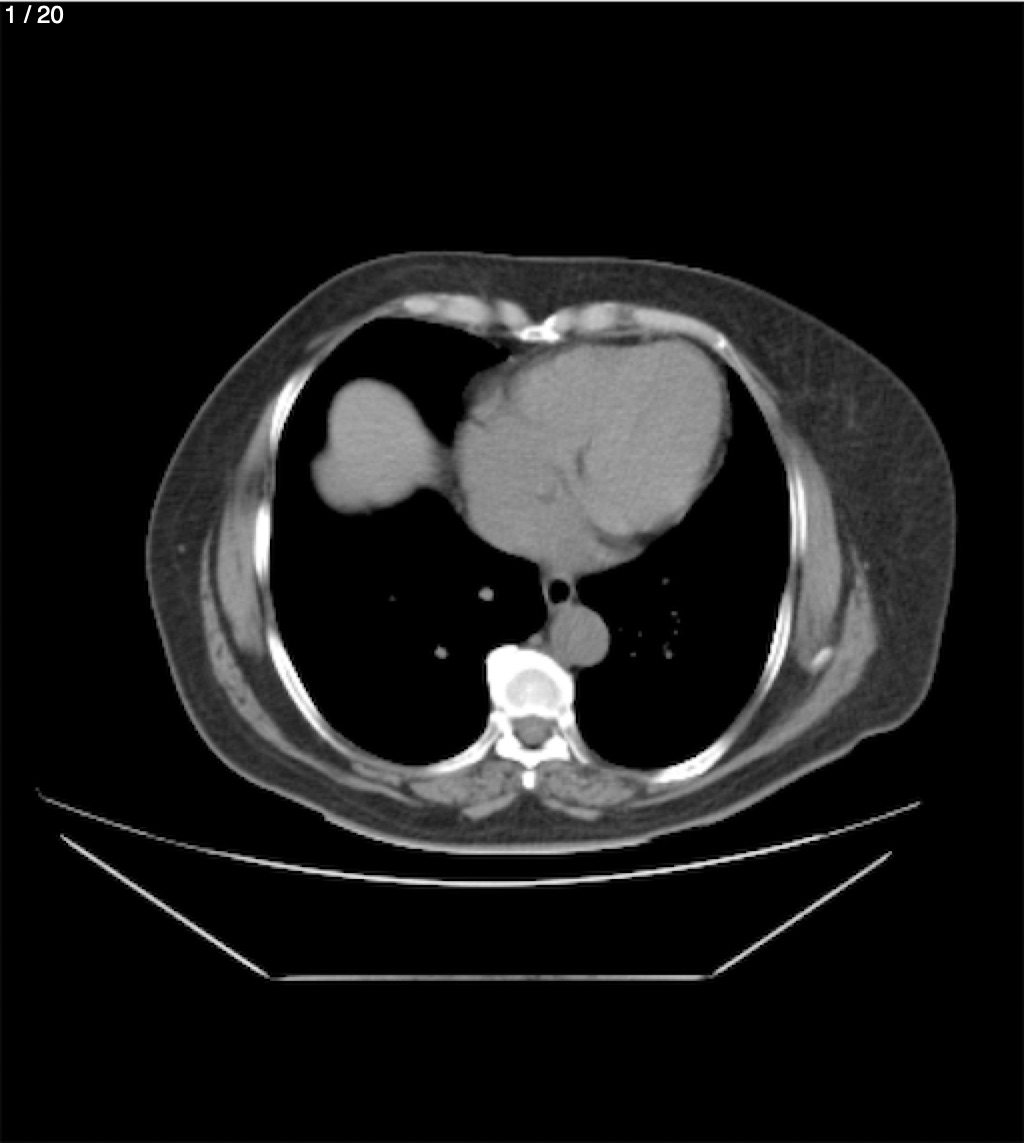

Maria Enrique Giron Dominguez63A - T.C Abdomen Simple